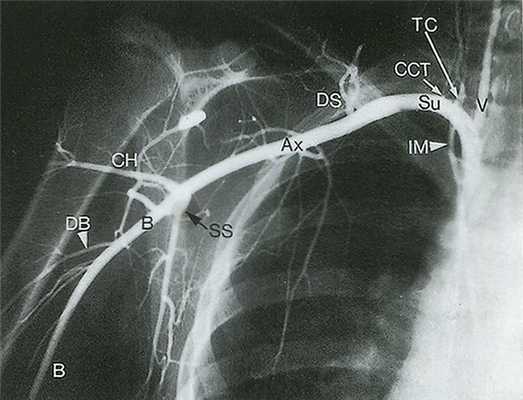

![Рис. 14.3. Подключичная артерия (Su) отходит от подмышечной артерии (Ах)]()

Рис. 14.3. Подключичная артерия (Su) отходит от подмышечной артерии (Ах) на уровне латерального края I ребра. Подмышечная артерия в свою очередь переходит в плечевую артерию (В) на уровне нижнелатерального края большой круглой мышцы. Заслуживают внимания такие ветви подключичной артерии, как щитошейный ствол (ТС) и реберно-шейный ствол (ССТ), поскольку при допплерографическом исследовании они могут быть ошибочно приняты за позвоночные артерии (V). Множественные ветви, кровоснабжающие мышцы лопатки, служат коллатералями при обструкции подключичной артерии или плечеголовного ствола. СН - артерия, огибающая плечевую кость; DB - глубокая артерия плеча; DS - дорсальная лопаточная артерия; IМ - внутренняя грудная артерия; SS - подлопаточная артерия.